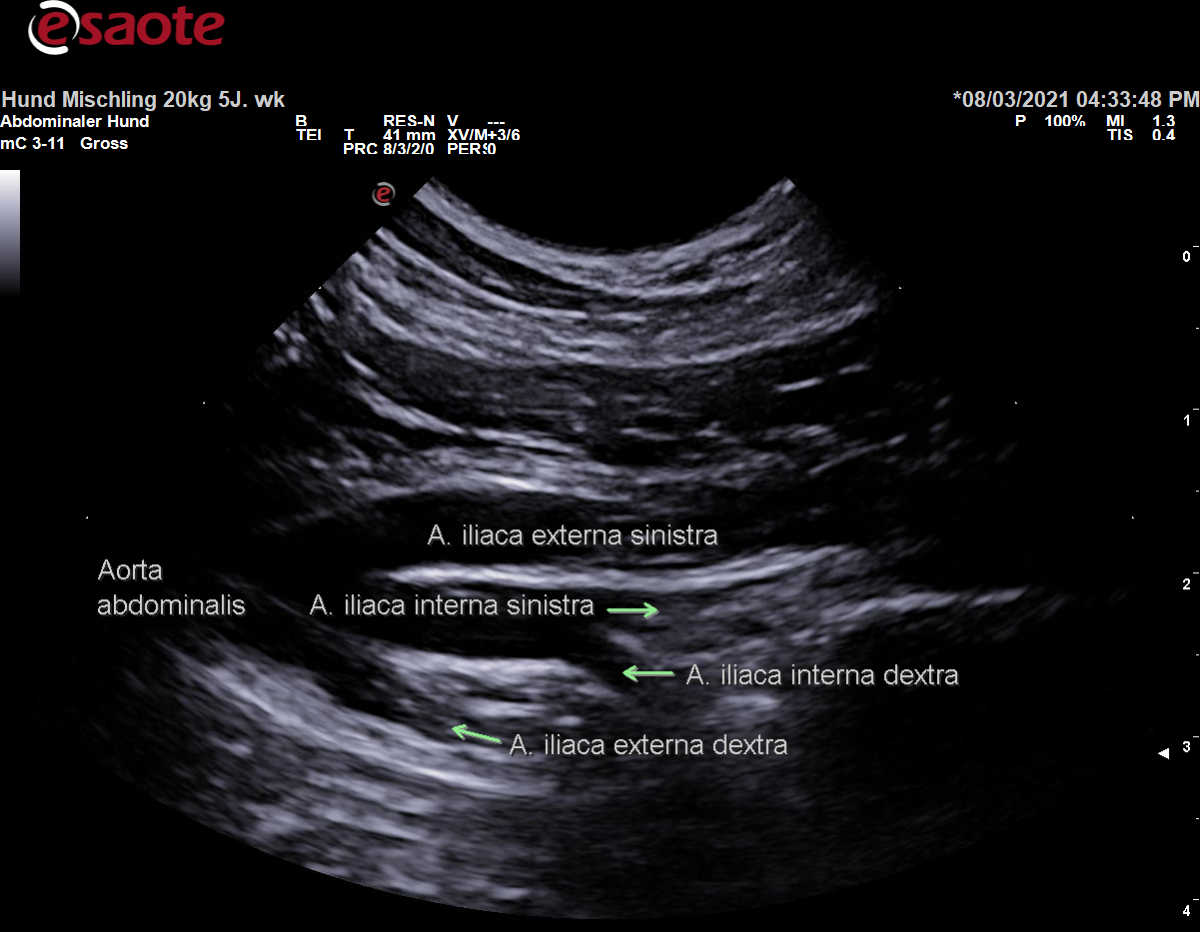

Ursprung der rechten und linken A. iliaca interna noch innerhalb der Bauchhöhle auf Höhe des 7. Lendenwirbels

Caudaler Verlauf über die ventromediale Fläche des M. iliopsoas in die Beckenhöhle

Bewegungsapparat und Organe der Beckenhöhle